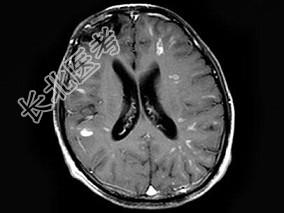

- 单项选择题男,26岁, 头痛、烦躁、意识障碍伴肢体活动障碍数天,头颅MRI检查见多发不规则小条片状结节状强化, 最可能的诊断是 ( )

A、脑结核

B、脑弓形虫病

C、化脓性脑炎

D、多发性硬化